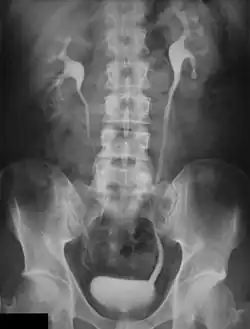

An intravenous pyelogram (IVP), also called an intravenous urogram (IVU), is a radiological procedure used to visualize abnormalities of the urinary system, including the kidneys, ureters, and bladder. Unlike a kidneys, ureters, and bladder x-ray (KUB), which is a plain (that is, noncontrast) radiograph, an IVP uses contrast to highlight the urinary tract.

An injection of X-ray contrast medium is given to a patient via a needle or cannula into the vein,[7] typically in the antecubital fossa of the arm. The contrast is excreted or removed from the bloodstream via the kidneys, and the contrast media becomes visible on X-rays almost immediately after injection. X-rays are taken at specific time intervals to capture the contrast as it travels through the different parts of the urinary system.[7] At the end of the test, a person is asked to pass urine and a final X-ray is taken.[7]

Immediately after the contrast is administered, it appears on an X-ray as a 'renal blush'. This is the contrast being filtered through the cortex. At an interval of 3 minutes, the renal blush is still evident (to a lesser extent) but the calyces and renal pelvis are now visible. At 9 to 13 minutes the contrast begins to empty into the ureters and travel to the bladder which has now begun to fill. To visualize the bladder correctly, a post micturition X-ray is taken, so that the bulk of the contrast (which can mask a pathology) is emptied.